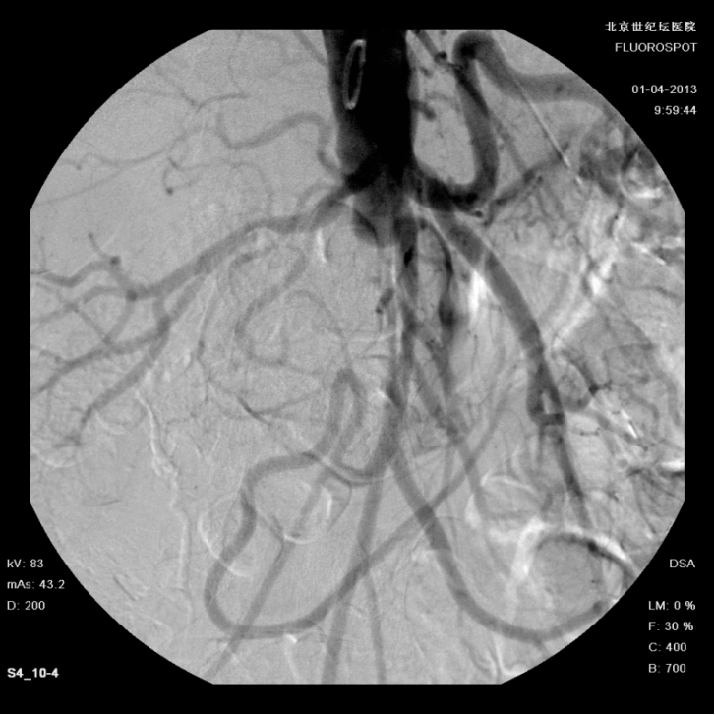

女性、61岁,病史:右下肢无力三个月

预置导管溶栓3天后效果明显

预置导管溶栓7天后效果满意并行支架术